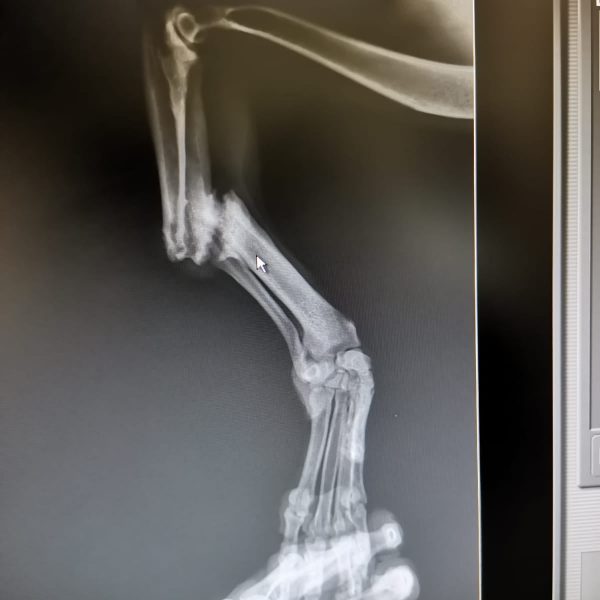

Immer wieder nehmen wir Hunde auf, welche keine Chancen haben. Finnley ist so einer. Er vertraut den Menschen (noch) nicht, jedoch beginnt er auf der Pflegestelle bereits Vertrauen zu fassen. Finnley muss wohl Unvorstellbares durchgemacht haben. Er hat ein gebrochenes Vorderbein, welches unter unsagbaren Schmerzen irgendwie zusammen gewachsen ist.

Als wir die Bilder aus Rumänien bekamen, konnten wir nicht absagen und holten ihn aus der Tötungsstation. Die OP- und Nachsorgekosten werden ca. 1500,– bis 2000– betragen. Spenden benötigen wir dafür dringend. Jeder gespendete Euro geht zu 100% an Finnley (Verwendugnszweck „Finnley“). Danke ![]()

Finnley wurde erfolgreich operiert (Fotos!) und nun steht einem schmerzfreien Leben nichts mehr im Weg. Die Operationskosten waren hoch, weshalb wir uns ganz speziell über Spenden für Finnley freuen!

Finley kam mit einem stark gebrochenen Vorderbein und großem Misstrauen den Menschen gegenüber bei uns an.